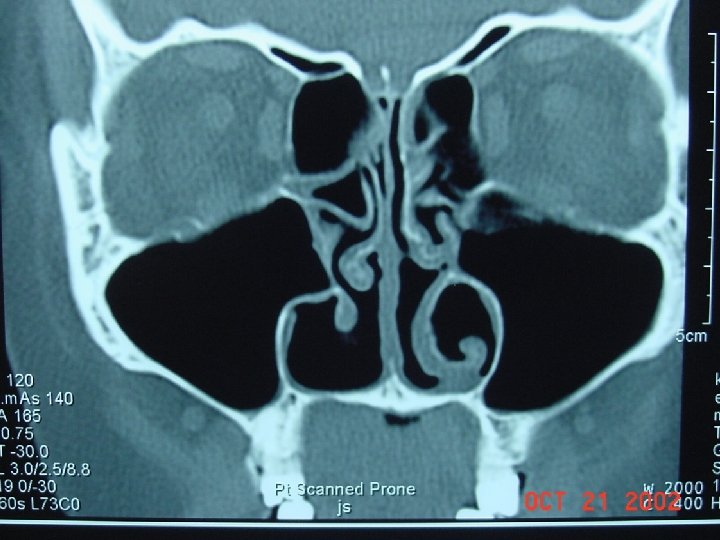

Diagnosis • Based on clinical signs and symptoms • Physical Exam: Palpate over the sinuses, look for structural abnormalities like DNS. • X-ray sinuses: not usually needed but may show cloudiness and air fluid levels • Limited coronal CT are more sensitive to inflammatory changes and bone destruction

Coronal computed tomographic scan showing ethmoidal polyps. Ethmoid opacity is total as a result of nasal polyps, with a secondary fluid level in the left maxillary antrum.